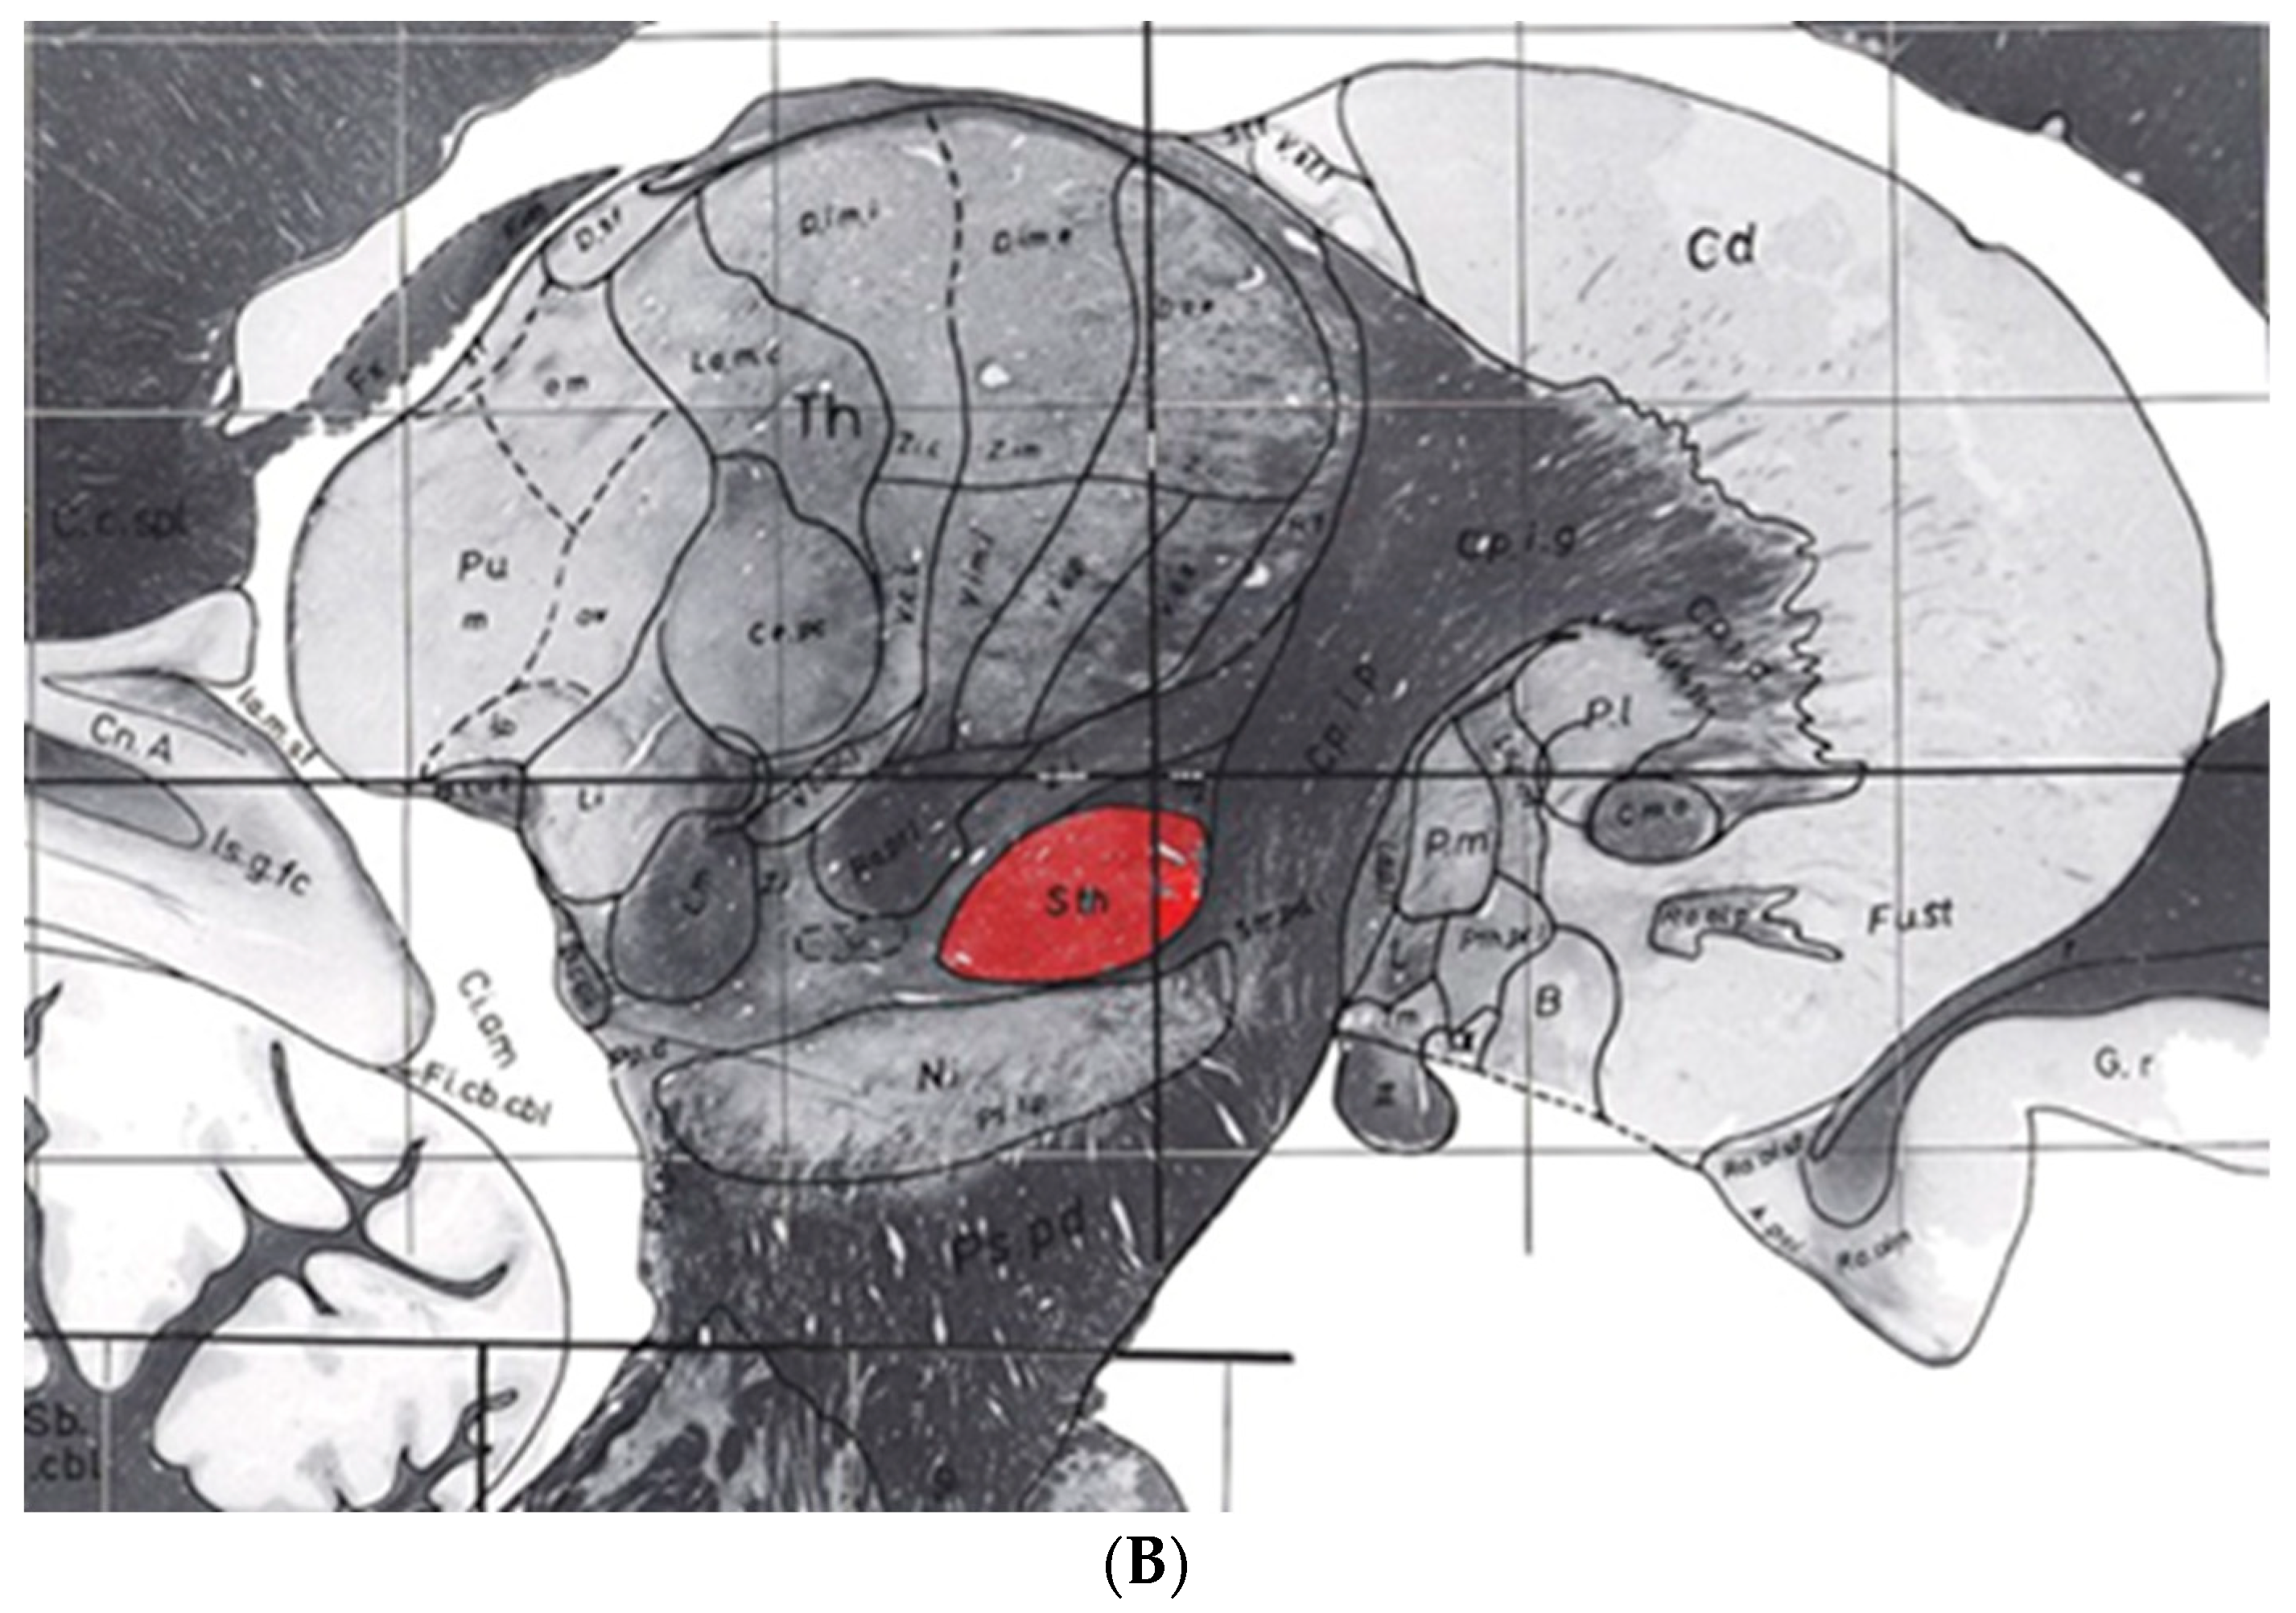

7.1. Consistencies and Inconsistencies of the Talairach and Tournoux 1988 and the Schaltenbrand and Wahren Atlases

- Niemann, K.; van Nieuwenhofen, I. One Atlas-Three Anatomies: Relationships of the Schaltenbrand and Wahren Microscopic Data. Acta Neurochir. 1999, 141, 1025–1038. [Google Scholar] [CrossRef] [PubMed]

- Nowinski, W.L.; Liu, J.; Thirunavuukarasuu, A. Quantification and Visualization of Three-Dimensional Inconsistency of the Ventrointermediate Nucleus of the Thalamus in the Schaltenbrand-Wahren Brain Atlas. Acta Neurochir. 2008, 150, 647–653. [Google Scholar] [CrossRef] [PubMed]

- Niemann, K.; Naujokat, C.; Pohl, G.; Wollner, C.; von Keyserlingk, D. Verification of the Schaltenbrand and Wahren Stereotactic Atlas. Acta Neurochir. 1994, 129, 72–81. [Google Scholar] [CrossRef]

- Nowinski, W.L.; Liu, J.; Thirunavuukarasuu, A. Quantification and Visualization of the Three-Dimensional Inconsistency of the Subthalamic Nucleus in the Schaltenbrand-Wahren Brain Atlas. Ster. Funct. Neurosurg. 2006, 84, 46–55. [Google Scholar] [CrossRef]